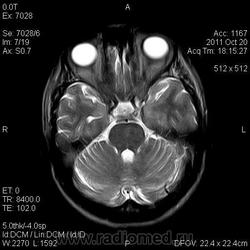

Центральный понтинный миелинолиз

Центральный понтинный миелинолиз — это особая форма демиелинизирующего процесса в области моста мозга, развивающаяся при быстрой коррекции гипонатриемии любой этиологии. Состояние впервые было описано при хроническом алкоголизме R. Adams в 1959 г. как осмотический демиелинизирующий синдром. Название «центральный понтинный миелинолиз» (ЦПМ) он получил позднее, когда был выявлен и при разных патологических состояниях — почечной недостаточности, сахарном диабете, булимии, печеночной недостаточности, аденоме гипофиза, вирусных инфекциях, системной красной волчанке, дефекте обмена мочевины, гастроэнтерите, длительной терапии диуретиками 1. Общим для них является наличие обменных сдвигов изменений водно-солевого обмена. ЦПМ встречается не только у взрослых, но и у детей.

Морфологически ЦПМ характеризуется распадом миелина в центральной части моста мозга с распространением на все проводящие пути за исключением латеральных отделов. Собственно аксоны, лишаясь миелиновой оболочки, не повреждаются. Развитие миелинолиза в других областях мозга получило название «экстрапонтинный миелинолиз» (ЭПМ). При ЭПМ очаги демиелинизации обнаруживаются в ножках мозга, зрительном бугре, мозолистом теле, не сопровождаясь воспалительной реакцией как при рассеянном склерозе.

На РКТ билатерально выявляются очаги пониженной плотности в мосту и других участках мозга, не сопровождающиеся контрастным усилением. Но следует заметить, что компьютерная томография не всегда способна выявить очаги поражения при данных патологических состояниях, особенно в его ранних стадиях.

МРТ в Т2W позволяет выявить равномерное повышение сигнала в зонах поражения мозга, иногда сопровождающееся снижением сигнала в зоне кортико-спинальных путей; в Т1W интенсивность сигнала в очагах поражения снижена, без признаков перифокального отека или объемного воздействия 1. Участок поражения моста визуализируется в виде овальной зоны на сагиттальных и аксиальных срезах и в форме крыльев летучей мыши на коронарных срезах. Покрышка моста и его вентролатеральные отделы не поражаются. Иногда очаг распространяется на средний мозг или на другие (экстрапонтинные) зоны: перивентрикулярное белое вещество, внутренняя и наружная капсулы, подкорковые узлы, таламус, коленчатые тела, а также белое вещество вблизи коры полушарий мозга и мозжечка. Признаки поражения на МРТ могут исчезать после клинического выздоровления.

Дифференциальный диагноз при рассматриваемой патологии должен проводиться прежде всего с опухолями мозга (глиомы, метастазы). Нужно иметь в виду также инсульты, рассеянный склероз, энцефалит и острый рассеянный энцефаломиелит, но эти заболевания обычно визуализируются в виде более диффузных очагов и отличаются от ЦПМ и ЭПМ клинически; паразитарные поражения моста и базальных ганглиев не бывают столь симметричными.